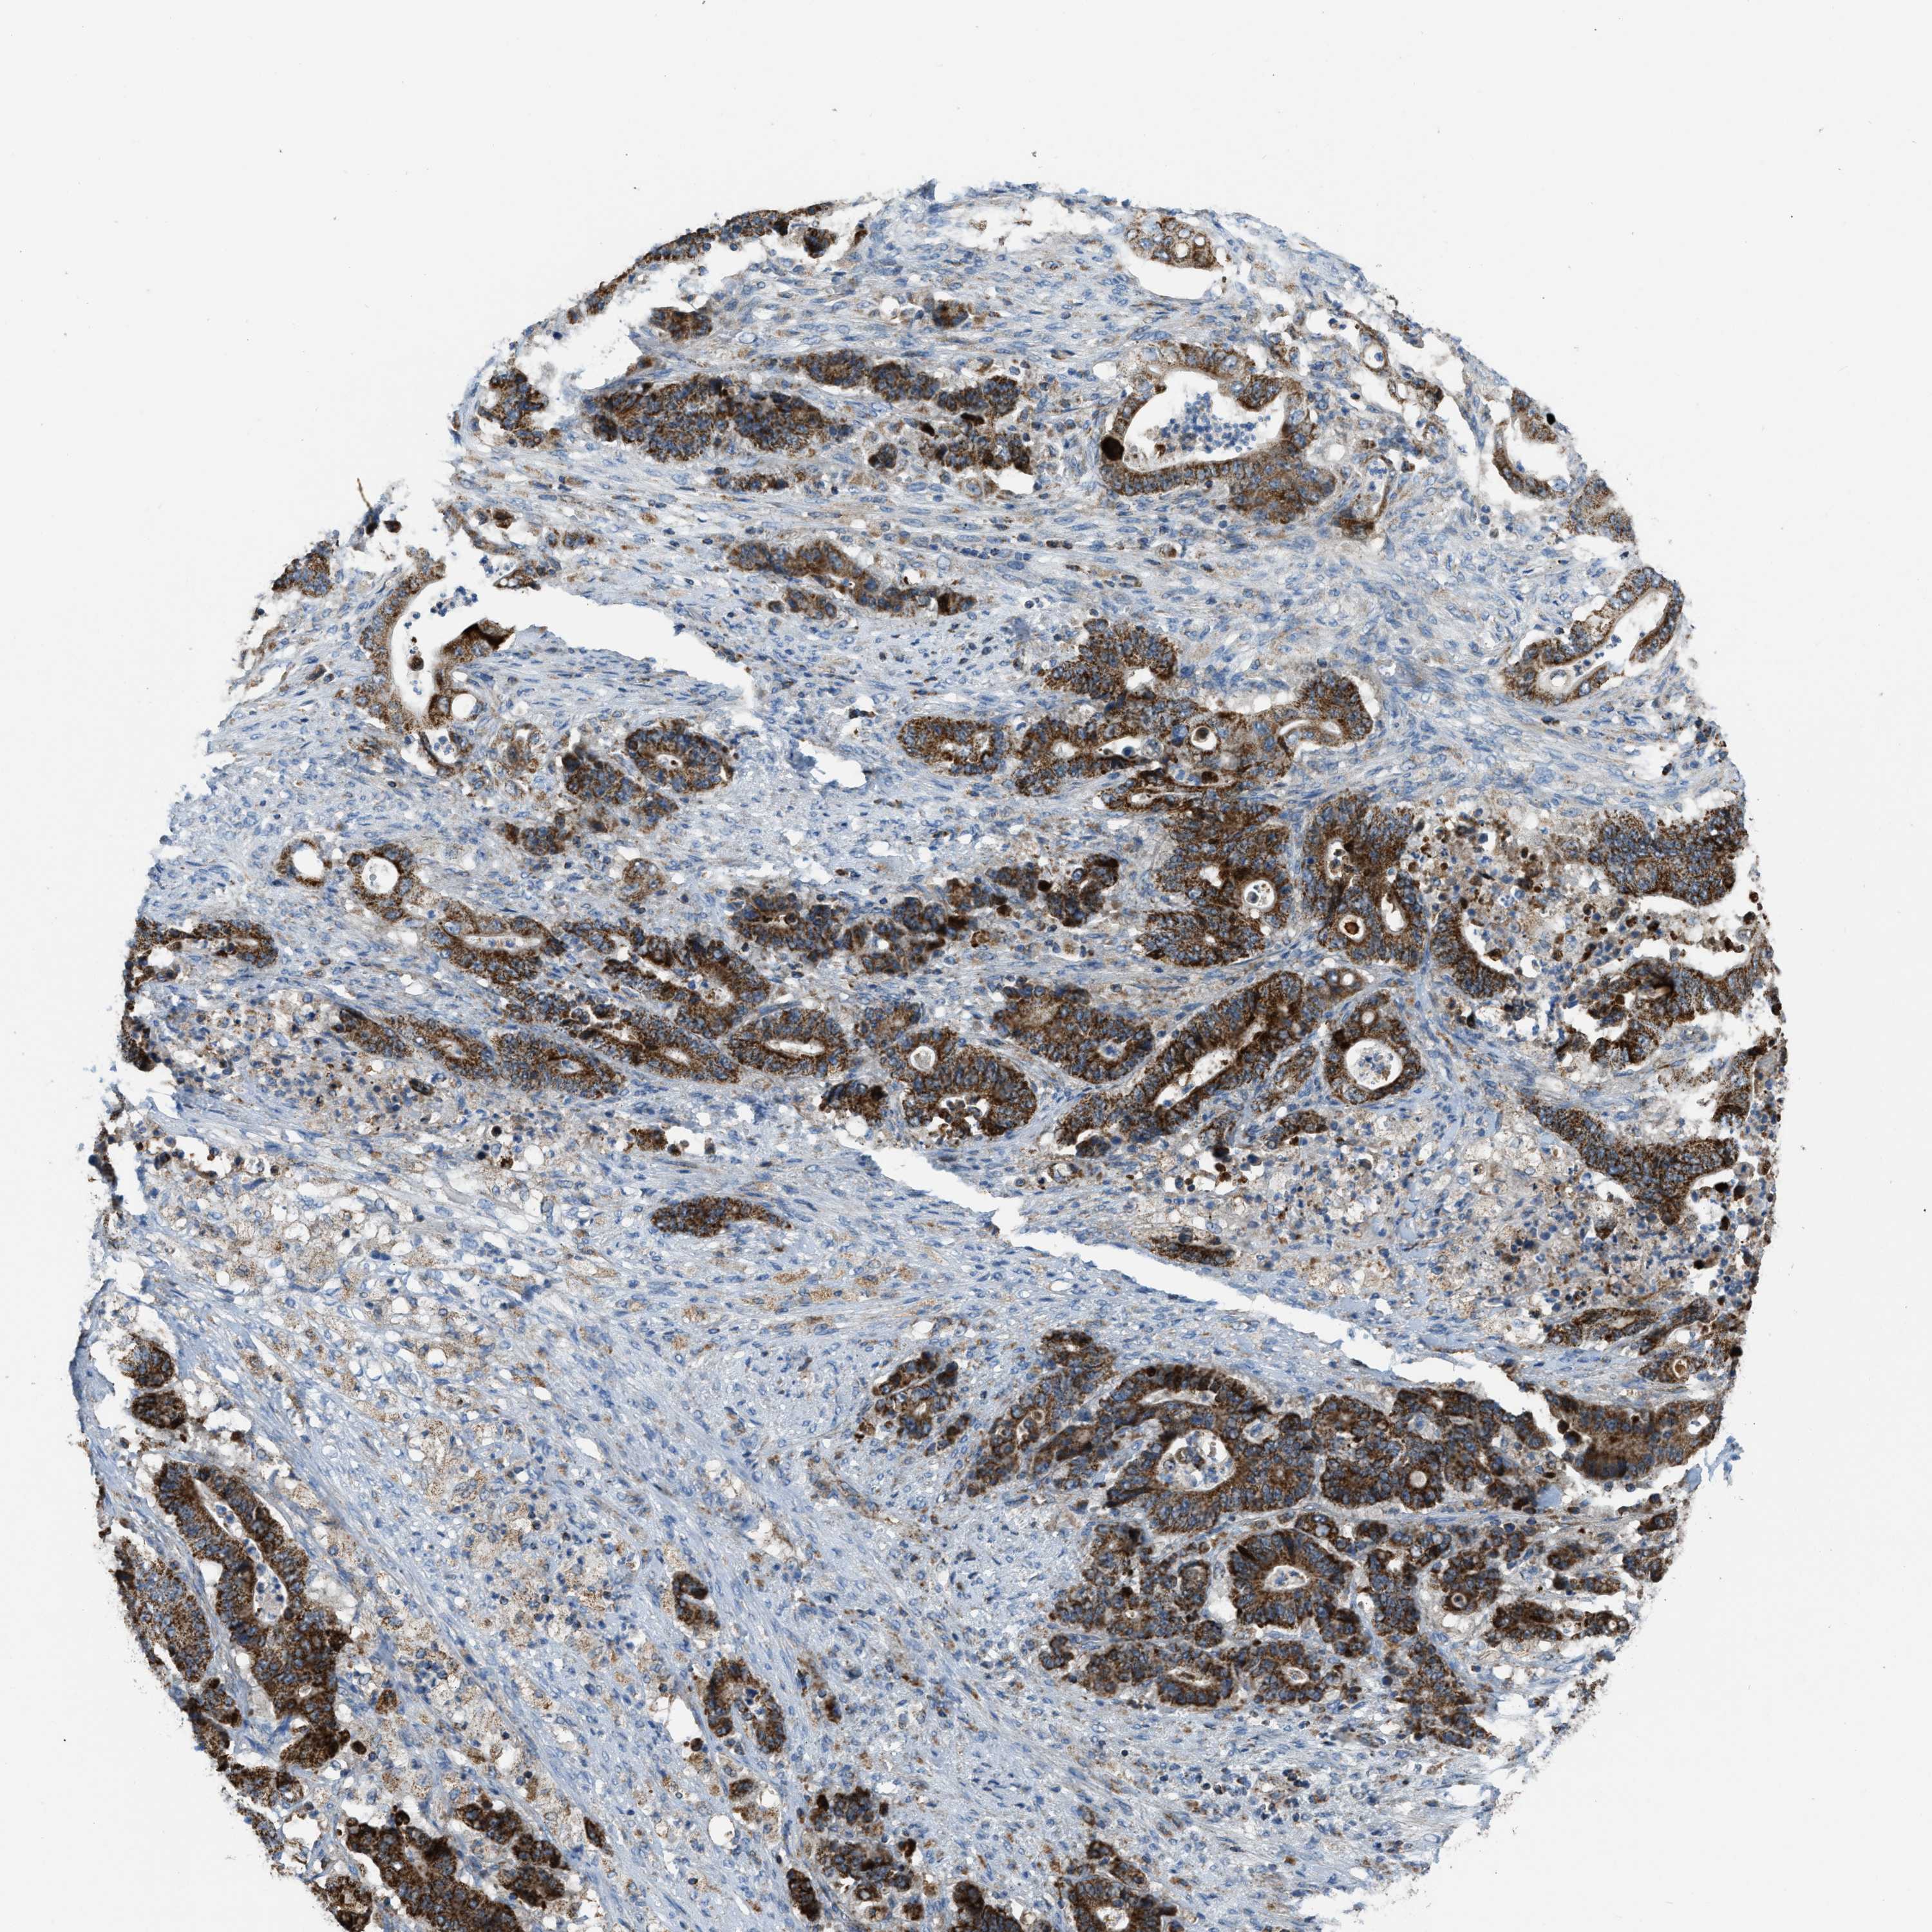

STOMACH CANCER - Protein expressioni

A mouse-over function shows sample information and annotation data. Click on an image to view it in a full screen mode. Samples can be filtered based on level of antibody staining by selecting one or several of the following categories: high, medium, low and not detected. The assay and annotation is described here.

Note that samples used for immunohistochemistry by the Human Protein Atlas do not correspond to samples in the TCGA dataset.

Antibody stainingi

Antibody staining in the annotated cell types in the current human tissue is reported as not detected, low, medium, or high, based on conventional immunohistochemistry profiling in selected tissues. This score is based on the combination of the staining intensity and fraction of stained cells.

Each image is clickable and will lead to virtual microscopy that enables deeper exploration of all samples and also displays staining intensity scores, fraction scores and subcellular localization as well as patient and tissue information for each sample.

Antibody HPA018910

Antibody HPA018921

Antibody HPA018923

Staining

High

Medium

Low

Not detected

Intensity

Strong

Moderate

Weak

Negative

Quantity

>75%

75%-25%

<25%

None

Location

Nuclear

Cytoplasmic/membranous

Cytoplasmic/membranous,nuclear

Adenocarcinoma, NOS